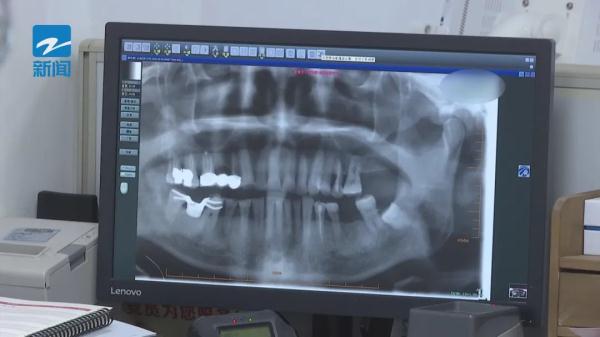

近日,不少细心的观众发现,比赛中谷爱凌嘴里咬了一个类似牙套的东西,比赛结束后,它则挂在了谷爱凌的胸前。记者从口腔医生那里了解到,这确实是个牙套,但不是用于矫正的,而是护齿牙套,它通常用比较软的硅胶制成,除了牙齿外,整个头部都可以受到保护。

在运动的过程中,牙齿一般是咬紧的,受到的外力会往上传。有时候运动导致上颌骨骨折,如果上颌骨没事,会传到脑部,产生脑震荡,通过护齿牙套,上下牙齿即便咬着,中间也会有缝隙,可以把受到的外力,往牙齿各个方向分散。

以滑雪运动为例,在速度比较快的情况下,如果滑雪者不慎摔了一跤,瞬间冲击力极大,如果没有戴护齿牙套,在巨大冲击力下,轻则牙齿断裂,严重时可能损伤舌头,甚至出现下巴骨折、牙齿被撞进骨头里等情况。医生介绍,目前,护齿牙套多见于专业运动员使用,普通人群几乎很少用。

那么,是不是普通人群真的就不需要护齿牙套呢?医生透露了一组数据:每年跟口腔有关的外科急诊中,有接近三分之一,是运动损伤导致的,而如果佩戴了护齿牙套,损伤完全有可能避免。

打篮球磕到的,还有轮滑磕到的,非常多,都是从下巴磕的,因为一个向前冲的力会磕到下颌骨,轻则下颌骨这里破了,软组织破裂,重则骨折,牙齿折断的、移位的,非常多。

医生提醒,进行剧烈运动,最好还是有意识的佩戴下护齿牙套。它和矫正牙套一样,护齿牙套可以根据每个人的口腔具体结构,进行个性化定制。